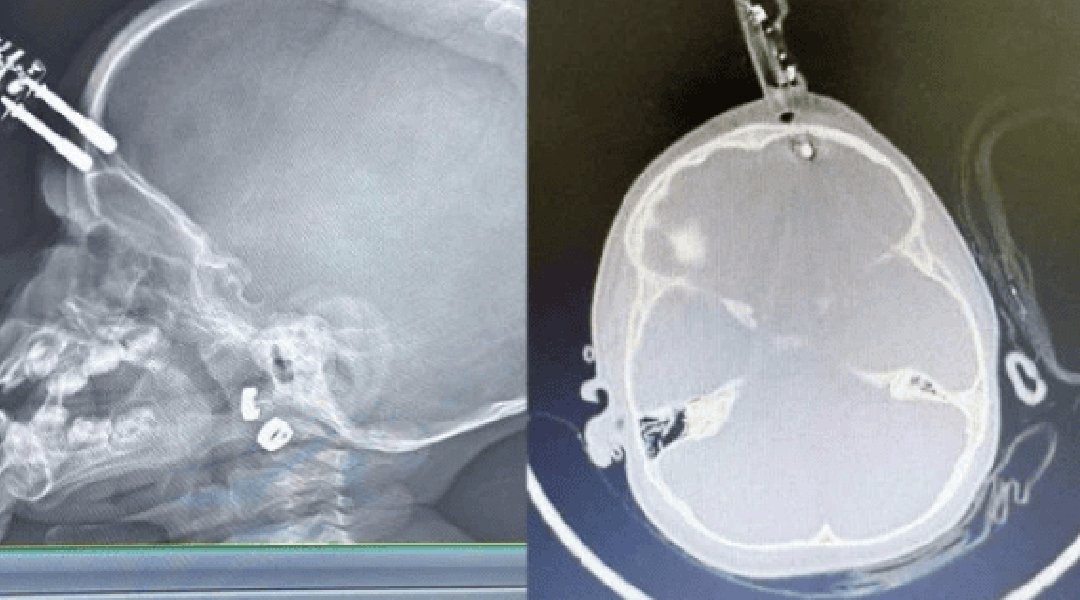

A criança foi levada inicialmente para a UPA de Divinópolis e, diante da gravidade, transferida pelo Samu para a sala vermelha do Hospital São João de Deus. Exames de imagem confirmaram que o pino havia transfixado o osso do crânio e atingido o cérebro. “O osso do crânio nessa idade é muito fino, tem apenas alguns milímetros. Pela tomografia, vimos que o objeto atravessou a calota craniana e lesionou a ponta do lobo frontal”, detalhou Bruno Castro.

Apesar da gravidade do ferimento, a criança estava consciente e foi levada imediatamente ao centro cirúrgico. O procedimento ocorreu sem intercorrências. “Foi uma cirurgia rápida e tranquila. Retiramos o corpo estranho, estancamos um pequeno sangramento e fizemos a correção da lesão. Ela acordou bem da anestesia e foi encaminhada ao CTI pediátrico”, afirmou o neurocirurgião.

A criança permaneceu 36 horas em observação intensiva e, após nova tomografia sem sinais de sangramento intracraniano, seguiu para a enfermaria. Por protocolo, recebeu antibiótico venoso durante cinco dias para prevenir infecções.